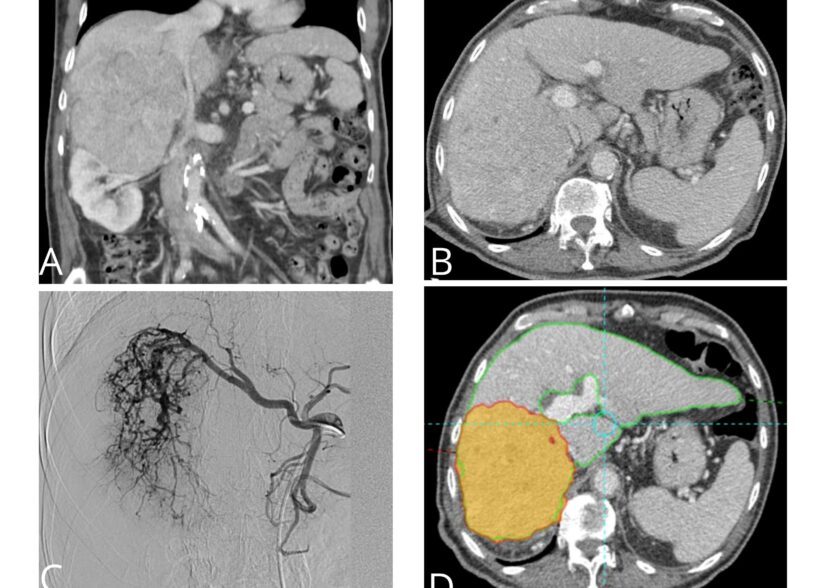

- Tumores hepáticos y otras lesiones oncológicas tratadas con técnicas locorregionales

- Embolización de tumores, miomas o sangrados

- Ablación de lesiones tumorales (radiofrecuencia o microondas)